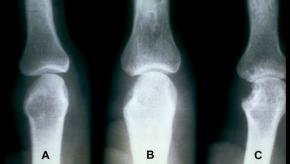

Read ArticleJAK Inhibitors Stimulate Osteoblasts